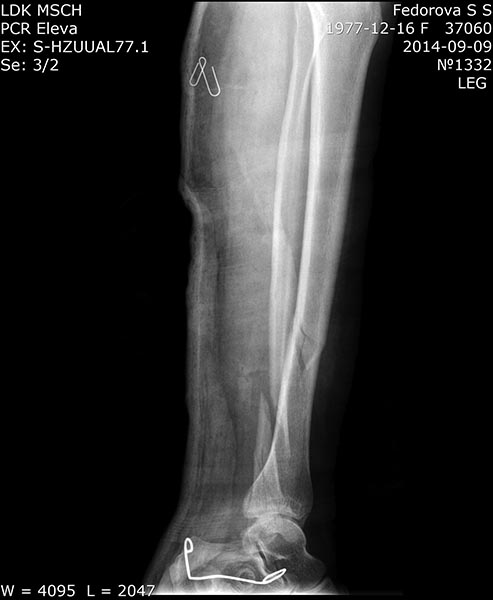

рентген2